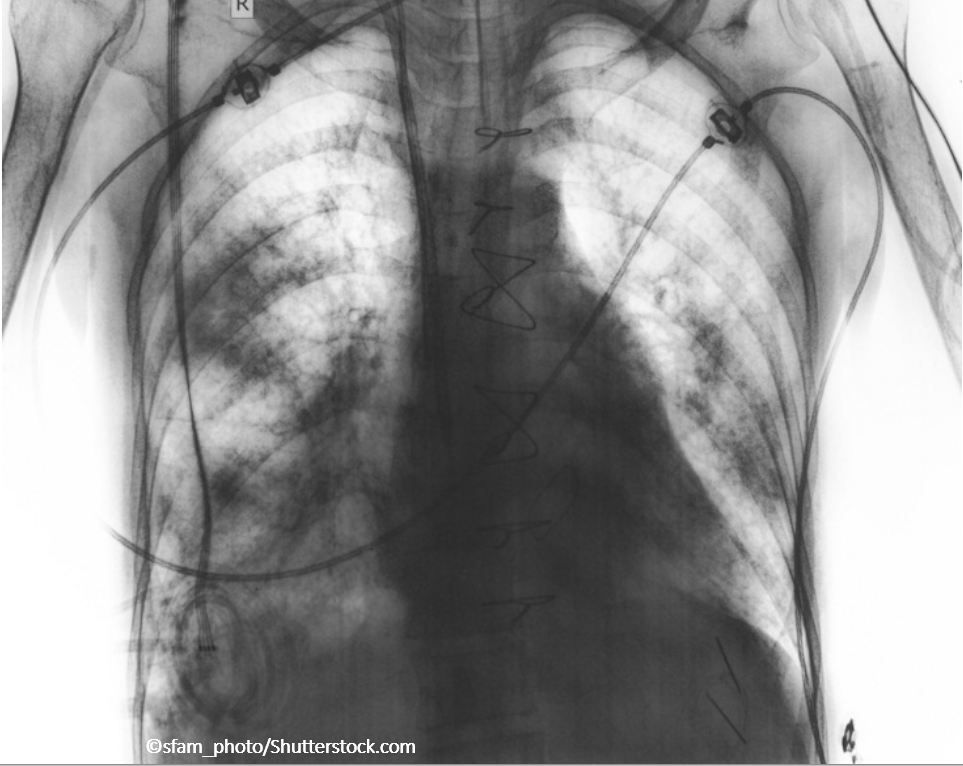

A pulmonologist answers some of the most common questions he hears from colleagues and students about COPD exacerbations and their management.